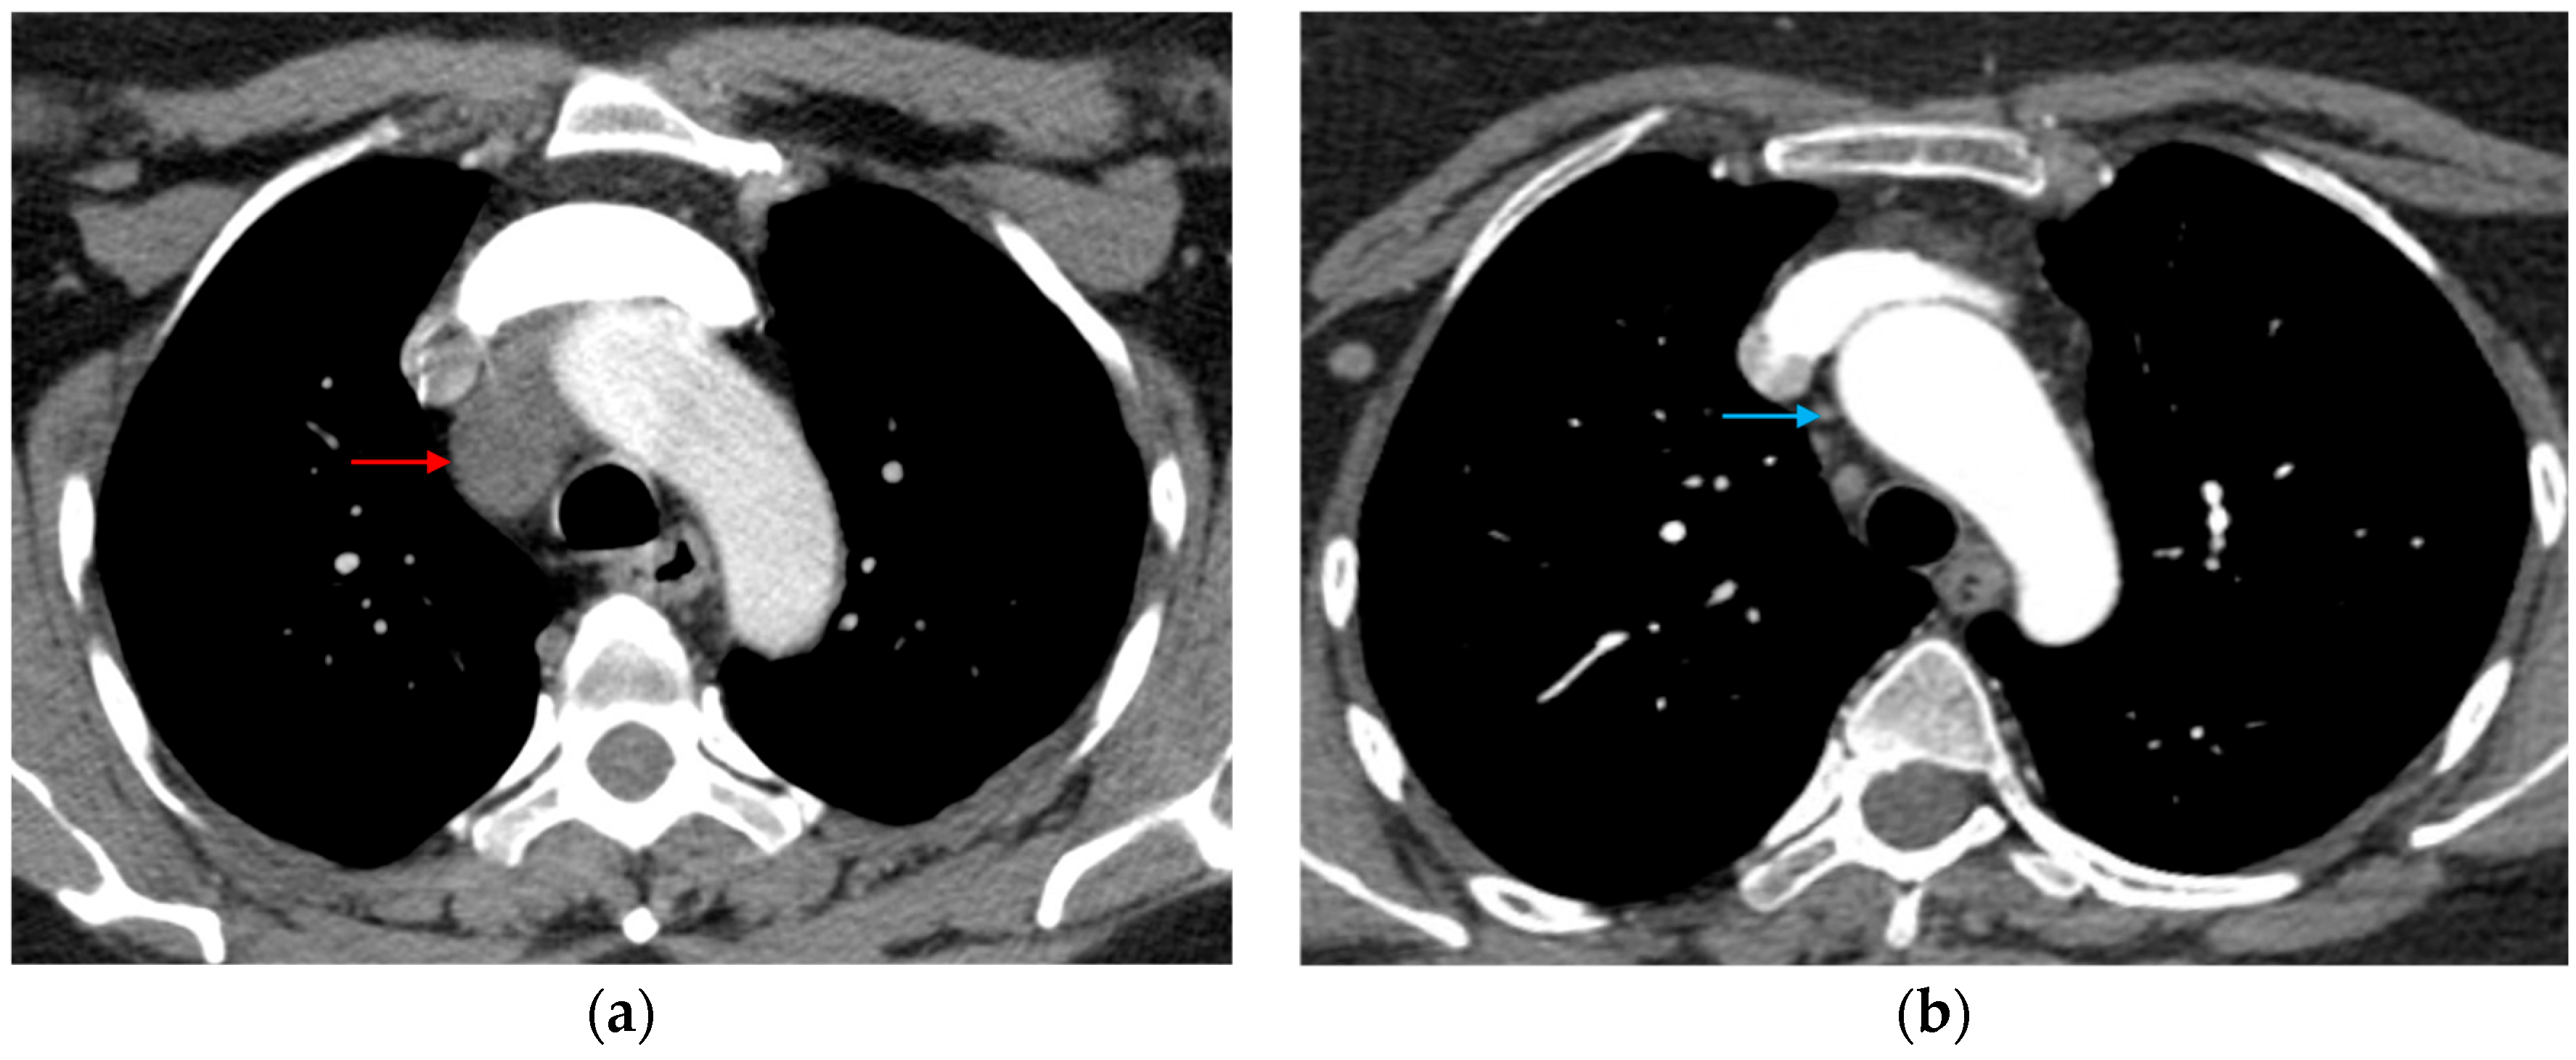

3.1.5. CT Angiography Artifacts

3.1.6. ECG-Gated CT Angiography

7.2. Complications Following Endovascular Repair